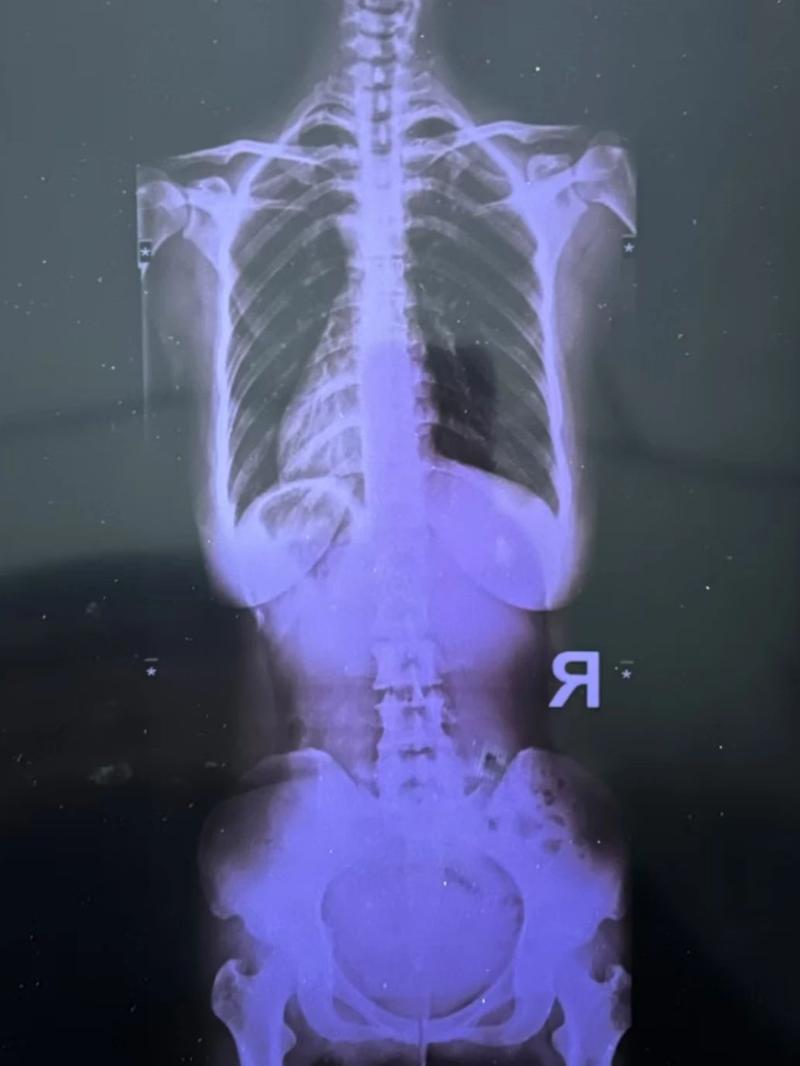

最近又疼起來(lái)嚴(yán)重影響正常生活,她前往醫(yī)院就診,結(jié)果查出了脊柱側(cè)彎11°,骨盆旋移,骶髂關(guān)節(jié)半脫位,由于這些導(dǎo)致頸肩,后背,腰部肌群代償出現(xiàn)問(wèn)題,從而出現(xiàn)腰痛,后背痛,肩膀痛!